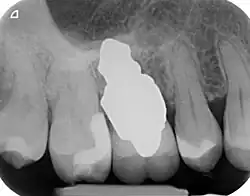

RAIs are custom made to perfectly fit the tooth socket of a specific patient immediately after tooth extraction. Therefore every implant is unique. As an optimised root-form it is much more than a simple 1:1 replica of a tooth. Since it exactly fills the gap left after the tooth is extracted, surgery is rarely needed. The implant can be produced from a copy of the extracted tooth, an impression of the tooth socket, or from a CT scan or CBCT scan.[7] The advantage of a CBCT scan is that the implant can be produced before extraction. With the former methods, it takes one or two days to fabricate an implant.

A root analogue implant can be fabricated from zirconium dioxide (zirconia) or titanium.[8] Successful titanium RAIs have been three-dimensionally printed as porous one-piece implants, using CAD software.[9] However, zirconia is the preferred material, because it is more esthetic in colour, with no grey discolouration visible through gums.[10][5]

- Natural form: a custom milled anatomic implant replicates the natural form of a tooth, so it simply fits into the tooth socket. Like the original tooth, a root analogue implant can have single- and multi-rooted forms.

- Esthetic: a ceramic RAI closely resembles a natural tooth in colour. Thus there is no discolouration through the gums, as is commonly seen with titanium implants.

A new attempt was made by Pirker et al 2004 in a human trial with root analogue zirconia implants, but this time by applying differentiated osseoingration on the surface. In 2011 he reported 90% success rate with this method in a 2.5 year human trial.[16]